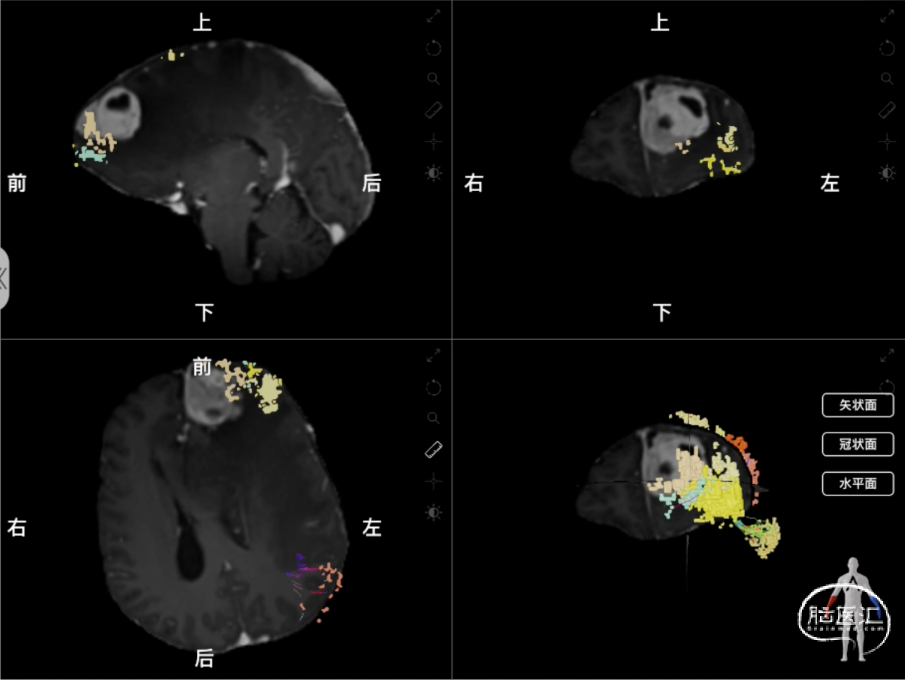

图2 术前使用Nura Surgical重建肿瘤与中央执行网络的关系,中央执行网络显示为黄橙色的彩色体素颗粒和彩色白质纤维束线条组成的整体(左上:矢状位;右上:冠状位;左下:轴位;右下:3D重建。)

图3:术前利用Nura Surgical重建肿瘤与白质纤维束的关系,彩色线条示皮质脊髓束,(左图:可见患侧皮质脊髓束受到瘤周水肿压迫向后移动且密度减低;右图:单独显示的皮质脊髓束结构)